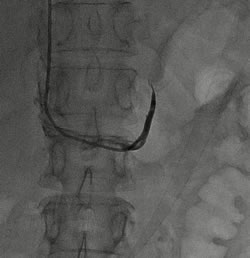

左侧肾上腺静脉插管采血 右侧肾上腺静脉插管采血

张女士是一名55岁的高血压患者,血压最高时可达180-190/100-110mmHg,使用3-4种降压药血压勉强控制到140/90mmHg以下。我院心血管专家团队为其进行了醛固酮立卧位试验,提示卧位ARR(血浆醛固酮/血浆肾素)53.1,立位ARR58.20,肾上腺CT增强发现其左侧肾上腺长有腺瘤。在中国高血压联盟副主席、我院心血管内科主任林金秀教授的指导下,彭峰博士和蔡瀚医师借鉴北京阜外医院与上海瑞金医院的先进经验,通过“双侧肾上腺静脉采血”为张女士进行肾上腺腺瘤功能评估。3天后,血液检查结果提示,其左侧选择性指数2.45,证明采血成功(选择性指数>2),左侧肾上腺静脉血醛固酮与外周静脉血醛固酮的比值,较左侧肾上腺静脉血皮质醇与外周静脉血皮质醇的比值未见明显升高,说明张女士左侧肾上腺腺瘤为无功能腺瘤,无需手术治疗,药物控制血压即可。最后,专家团队悉心为张女士的用药进行了调整,在血压的到良好控制后,张女士顺利出院。